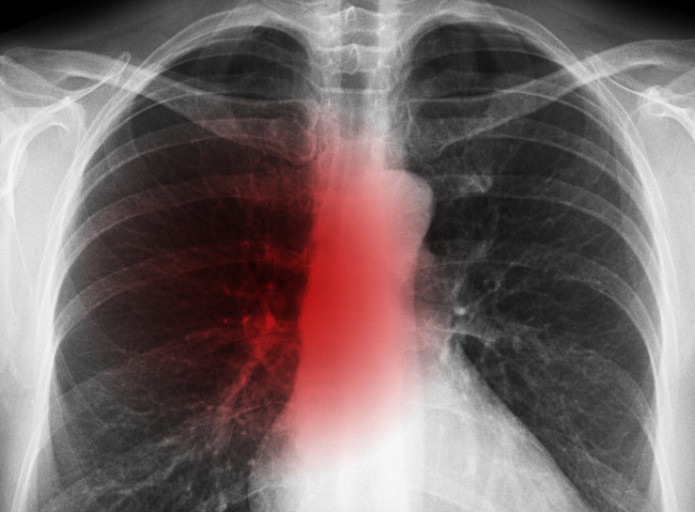

폐렴 증상을 겪는 그럴 경우 X선 촬영 및 배양 검사로 진단할 수 있어요. 필요에 따라 소변, 혈액, 혈청 검사, CT 등을 추가로 실시해요. 폐렴 진단을 받은 환자는 일반적으로 입원을 권장하지 않지만 젊거나 기초질병이나 호흡곤란이 심한 그럴 경우, 고령, 임신 등의 그럴 경우 전문기관에 방문해서 상황에 맞는 신속한 치료와 상태 개선, 위험예방을 받는 것이 좋아요. 폐렴 증상의 치료에서 가장 주요한 것은 항생제로 원인균을 제거하는 것인데요. 세균이나 바이러스 감염에 의해 발생하며 처음에는 항바이러스제를 통해 감기처럼 치료하기도 해요.